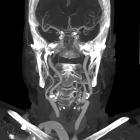

Ultrasound with Doppler interrogation is an efficient and accessible method to assess it and is usually the initial study. It will show the bifurcation of the brachiocephalic artery into the right common carotid artery and right subclavian artery located superior to the right sternoclavicular joint (normally located behind it). The bifurcation can be as high as the inferior part of the right lobe of the thyroid gland.

CT, MRI, and angiography will show further details as the brachiocephalic artery ascends above the thoracic inlet before bifurcating.